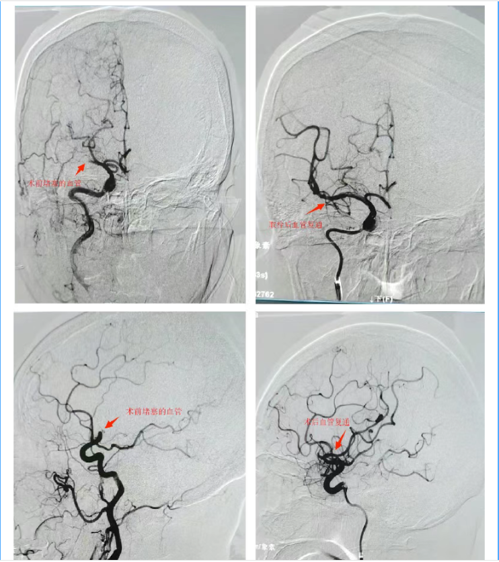

2.神经介入创新技术:在广西区内率先开展经(远)桡动脉途径全脑血管造影及介入诊疗技术,引领脑血管微创介入新方向;擅长复杂脑血管造影术、脑血管腔内成形术/支架植入术、颅内动脉瘤栓塞等介入治疗,积累丰富临床经验;采用BASIS技术一站式处理颅内动脉狭窄合并远端栓塞,减少器械交换次数,降低血栓逃逸及血管损伤风险;应用新型血流导向装置技术治疗颅内动脉瘤,通过血流重建实现病变血管修复,减少动脉瘤复发率;利用OCT血管内光学相干断层成像在颈动脉支架术中的精准评估,显著提升手术安全性与疗效。

(一)脑血管病及介入诊疗

依托国家高级卒中中心平台,开通急性卒中救治“绿色通道”,精准筛选静脉溶栓、动脉取栓治疗适应人群,立急性缺血性卒中静脉溶栓、动脉溶栓及机械取栓的一体化救治体系,开展颅内外动脉狭窄血管成形术、支架植入术及颅内动脉瘤栓塞术等介入技术,并牵头国内外新药临床试验及创新技术研发,尤其擅长经(远)桡动脉入路神经介入治疗,以微创化、低并发症的显著优势提升患者预后。

经桡动脉脑血管造影

脑梗死急诊取栓术后再通

动脉瘤栓塞术